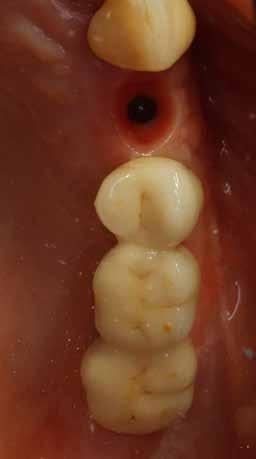

A fogpótlás készítésének lépései

Hathetes gyógyulás után a lágyszövetek kiválóan gyógyultak, és minden implantátum megfelelően osszeointegrálódott, amelyet a radiológiai vizsgálat is megerősítetett (9. és 10. ábra).

Nyitott kanalas lenyomatvételi fejeket csatlakoztattunk az implantátumokhoz, és elasztomer lenyomat-anyagot fecskendeztünk köréjük és a lenyomatkanálba, hogy egyfázisú lenyomatot vegyünk. A minta laboratóriumi elkészítését követően a kimart vázra kerámia leplezés került, amelyet megfelelő festéssel tettek még természetesebbé. Ezt követően a pótlást közvetlenül az implantátumokhoz csatlakoztattuk, majd ellenőriztük a kontaktpontot és az okklúziót. Minden csavart 35 Ncm-es nyomatékra húztunk, majd a csavarnyílásokat teflonszalaggal és fényre kötő kompozittal zártuk (11. ábra).

10. ábra: Lágyszövetek a hat hét gyógyulást követően.

11. ábra: Az elkészült híd a szájban – okkluzális nézet.

12. ábra: A végső radiológiai vizsgálat megerősítette az osszeointegrációt és a pótlás optimális illeszkedését.